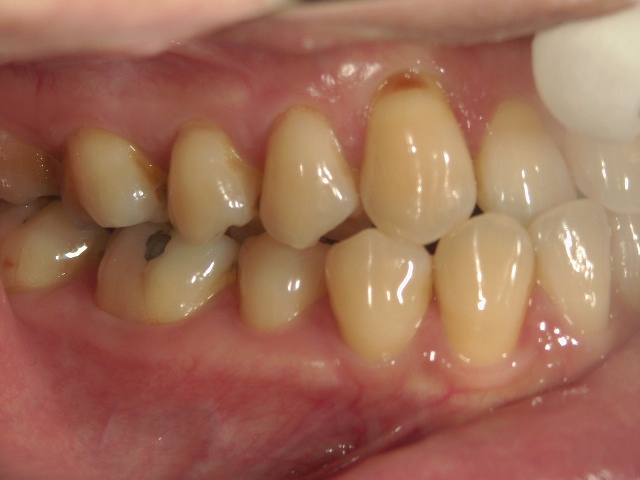

矯正歯科 治療前 右

矯正歯科 治療前 左